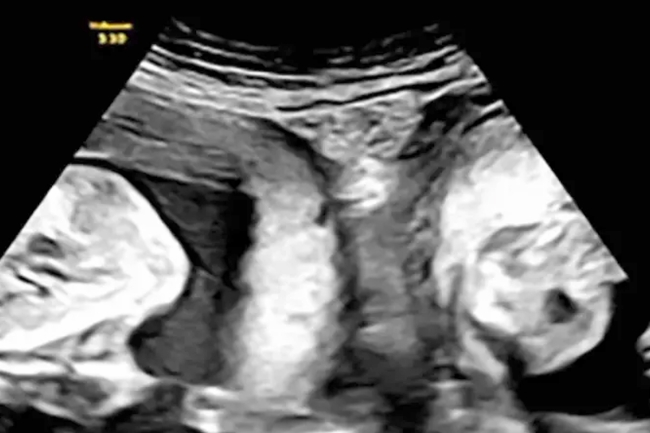

صينية برحمين أنجبت توأمين

أنجبت امرأة تعاني حالة نادرة بامتلاكها «رحمين»، توأمين، واحد من كل رحم، في مستشفى بشمال غرب الصين. وفي الحدث الذي وصف بأنه «واحد في المليون»،